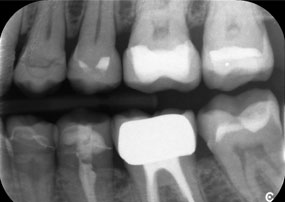

Dr. Wolfgang Tautschnig, ein erfahrener Zahnarzt aus Salzburg, hat die Synea Power Edition über mehrere Monate hinweg in seiner Praxis in verschiedenen klinischen Szenarien eingesetzt und evaluiert. Darunter vor allem für das Entfernen von Zirkonkronen und das Bearbeiten von unedlen Legierungen. In einem konkreten Fall stellte sich eine 81-jährige Patientin mit dem Wunsch nach einer ästhetischen Verbesserung ihrer 40 Jahre alten VMK-Kronen vor. Die bestehenden Kronen entsprachen nicht mehr den ästhetischen Ansprüchen der Patientin. Die Herausforderung lag in der Entfernung von zwölf verblockten Kronen mit unedler Legierung, ohne die darunterliegenden Zahnstümpfe zu beschädigen. Das Winkelstück wurde genutzt, um die Keramikschichten präzise einzuschlitzen sowie die Metallgerüste mit einem Hartmetallfräser zu trennen, um so die Kronen mit minimalem Trauma zu entfernen. Innerhalb von nur 30 Minuten waren die alten Kronen entfernt, danach konnte die neue Arbeit, bestehend aus Vollzirkon im Seitenzahnbereich und verblendeten Kronen im Frontzahnbereich, vorbereitet werden. Das Ergebnis war eine vollständige Neuanfertigung, die sowohl funktional als auch ästhetisch überzeugte (siehe Abb. 1).

Ein Kiefer-Röntgenbild einer 81-jährigen Patientin vor schwarzem Hintergrund.

Abbildung 1: Ästhetische Rehabilitation von VMK-Kronen: Vollständige Entfernung und Ersatz von 40 Jahre alten VMK-Kronen zur ästhetischen Verbesserung bei einer 81-jährigen Patientin.